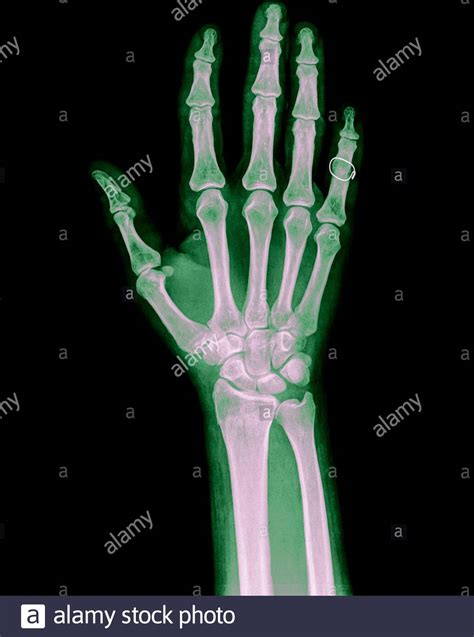

A broken hand, often diagnosed through an X-ray, involves a fracture in one or more of the bones in the hand. The hand is composed of 27 bones, including the metacarpals, phalanges, and carpals. Each of these bones can be susceptible to fractures, which can range from minor cracks to severe breaks.

• X-rays: X-rays are the primary imaging tool used to confirm the presence and type of fracture. They provide detailed images of the bones and can help determine the severity of the injury.

• fractured finger x ray